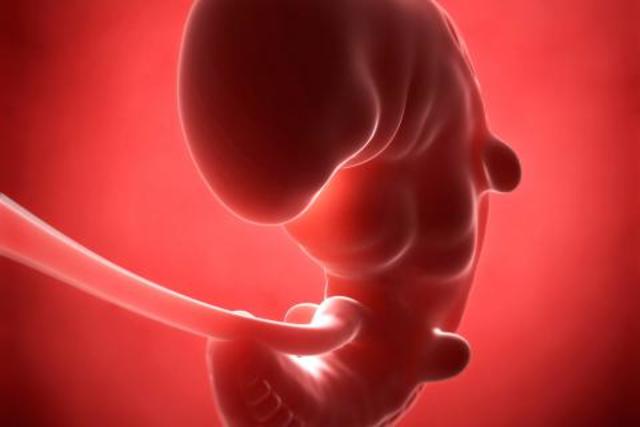

• Semana 2

Semana 2

Se desarrolla lo que denominamos embrión, que tiene, básicamente, una cabeza, un tronco y una cola rizada.

Esta semana de embarazo está marcada por:

- La sujeción del blastocisto en el útero, ya que va a ser su “casa” durante todo el embarazo.

- La creación del saco o cavidad amniótica incluido el líquido amniótico..

- La cavidad coriónica, donde estará fijado el embrión sobre un pedículo de fijación, que se transformará en el cordón umbilical.